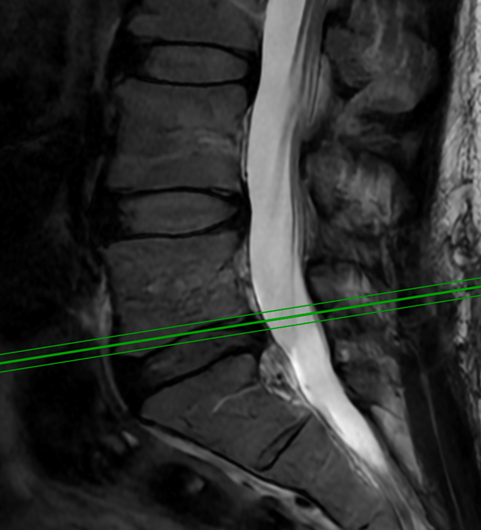

Minimally Invasive Spine Surgery Treats Acute Leg and Foot Weakness